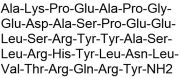

| 14:23, 22 באוגוסט 2023 | PYY 3-36-1.jpg (קובץ) |  |

41 קילו־בייטים | Motyk | 1 | |